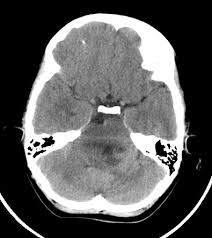

Компьютерная томография не является базовым исследованием для диагностики глиомы головного мозга, потому что метод не позволяет оценить степень инфильтрации опухоли, состояние спинномозговой жидкости, зону перифокального отёка и характеристики сосудистой инвазии. Глиома представляет собой первичную опухоль центральной нервной системы с преимущественно инфильтративным ростом и выраженными мягкотканевыми изменениями. Для диагностики назначаются магнитно-резонансная томография с диффузионно-взвешенными и перфузионными режимами и контрастированием. Оданко КТ выявляет следующие анатомические признаки:

В нативном режиме визуализируется гипо- или изоденсный очаг в веществе мозга, чаще с нечёткими границами и признаками отёка.

В режиме сканирования мягких тканей фиксируется деформация и уплощение желудочков, асимметрия борозд и сдавление мозговых цистерн.

В режиме с контрастированием определяется участок умеренного или кольцевидного усиления, характерный для глиобластомы, при этом низкодифференцированные глиомы могут не накапливать контраст.

В режиме высокоразрешающего сканирования костных структур могут выявляться признаки хронического внутричерепного давления, остеоперестройки или кальцификатов в опухоли.

Определяются признаки внутричерепной гипертензии, гидроцефалии и возможного вклинения при выраженном объёмном эффекте.